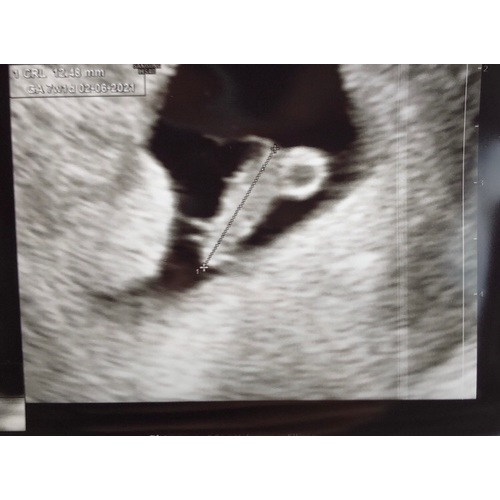

Hi! Hier een zelfde soort verhaal. Ik heb al 2 weken last van bloedingen, wat overging in rood, tot vrijwel niks. Ik had een spoed echo vorige week do en daarop was niks afwijkends te zien. Maar omdat erna het bloed verlies toe nam, ging ik van het ergste uit en dacht ij dat er een miskraam in werking was gezet. Maar dit bloedverlies werd na 1 middag minder en werd weer bruinverlies. Afgelopen do had ik de vitaliteitsecho al staan, en wist ik niet wat ik kon verwachten. (De bloedingen zetten niet door....) tijdens deze echo was er ander weefsel te zien (bloedstolsels) maar ook een kleine embryo met een kloppend hartje in een mooi vruchtzakje! Ik kon het niet geloven. Mijn angst voor een miskraam viel wel weg, alleen kwam daar wel weer een andere zorg naar boven en dat is; wat is het dat er nig meer in mijn baarmoeder zit wat er niet hoort. Ik blijf positief omdat het kindje dus wel veilig zit en dus groeit en leeft! De VK had het over dat het wellicht een vleesboom ziu kunnen zijn. Ik ben doorverwezen naar de gynaecoloog in het ziekenhuis. Hopelijk as week hierover meer duidelijkheid.

Hi paap, ik ben nu 7+2, als het goed is. Omdat ik maar bruin verlies blijf houden heeft mn VK er wel haast bij gezet...het rare is dat de 1e keer de echoscopiste dus niks afwijkends heeft gezien. Een week later dus wel en is er aan de bel getrokken. Zelf neig ik naar dat het misschien 2 vruchtjes zijn geweest ( en dat we bij de eerste echo dus het ‘slechte’ vruchtje hebben gezien, en het goede dus helemaal niet is gezien door haar) Een week later ineens veeel groter dan de 1e keer + kloppend hartje, maar dus met veel stolsels in mn baarmoeder erbij....maar ik ben geen dokter, dus voor nu blijft het gissen....